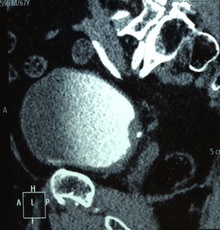

Из анамнеза: с 2013 года периодически отмечает примесь крови в моче с бесформенными сгустками. По месту жительства, при УЗИ выявлено образование мочевого пузыря в области правого устья размером 30*9мм. Выполнена компьютерная томография органов брюшной полости и малого таза, по данным которой образование подтвердилось. Пациент был направлен в клинику урологии Первого МГМУ им. И.М. Сеченова. Госпитализирован для дообследования и определения дальнейшей тактики лечения.

Рис. №2. Мультиспиральная компьютерная томография органов мочевой системы с контрастированием.

Пациенту выполнена трансуретральная электрорезекция стенки мочевого пузыря с опухолью и дренирование ВМП катетером-стентом.